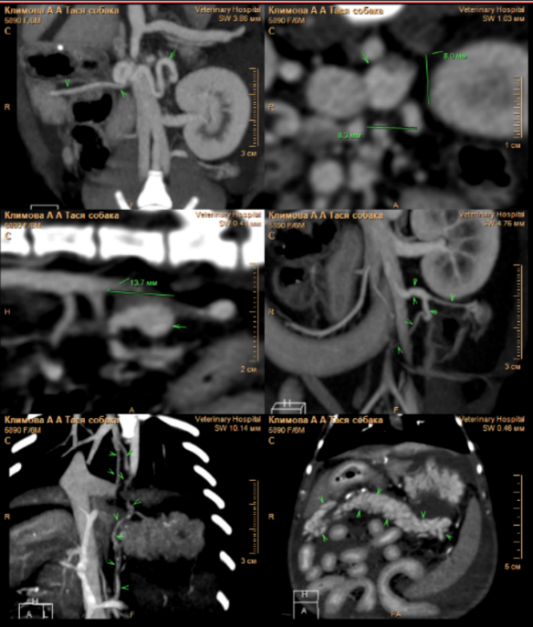

В этот период состояние пациента ухудшилось (фото 3), прогрессировал более выраженный асцит. Это привело к затруднению двигательной активности собаки, и владельцы приняли решение о повторном проведении ультразвукового исследования брюшной полости.

В ходе проведения УЗИ выявлена отрицательная динамика в отношении количества свободной жидкости в брюшной полости (до 6 см на просвет). Также обнаружены увеличение отека паренхимы поджелудочной железы, характеризующееся появлением признаков, известных как «тигровая поджелудочная железа», и нефролитиаз (фото 4). Данные изменения свидетельствуют о развитии тяжелой портальной гипертензии, что требует проведения незамедлительной диагностики для установления причин и разработки плана лечения.